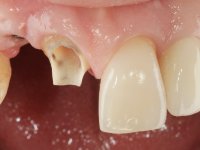

Primeira Fase.

O dente 1.1 foi preparado para uma coroa total, o afastamento gengival foi feito com caolino comprimido pela restauração provisória. A impressão foi feita com uma técnica de dupla mistura com dupla viscosidade. No laboratório foi confecionada uma coroa com infraestrutura em Zr revestida por cerâmica. A coroa foi cimentada em boca com cimento de ionómero de vidro reforçado por resina.